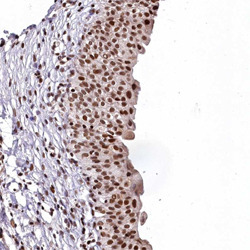

Supportive validation

- Submitted by

- Abnova Corporation (provider)

- Main image

- Experimental details

- Immunohistochemical staining of human urinary bladder with FAM217B polyclonal antibody (Cat # PAB27892) shows strong nucleaar positivity in urothelial cells at 1:50-1:200 dilution.

- Validation comment

- Immunohistochemistry (Formalin/PFA-fixed paraffin-embedded sections)